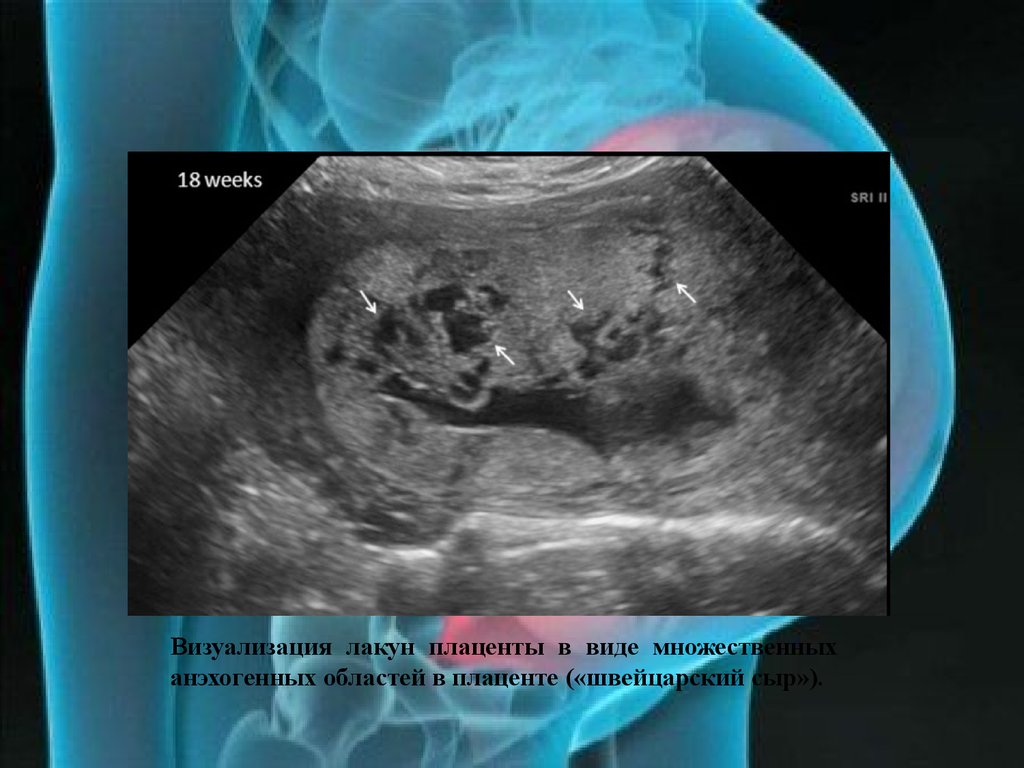

Медицина и диагностика: Инвазивный пузырный занос на УЗИ